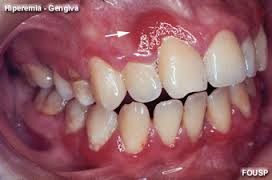

Esta é uma situação periodontal crítica. Periodontite inflamatória generalizada. O incisivo central direito, não tem mais osso por vestibular, está com mobilidade 3, isto é, condenado.